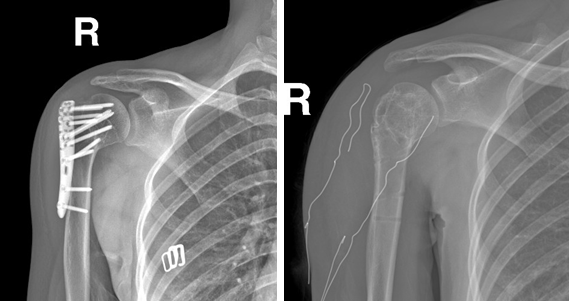

病例一:

女性22岁,车祸伤右肱骨近端骨折并肱骨头脱位,行切开复位钢板螺钉内固定手术。

术前                         术后

术后1年取内固定

术后